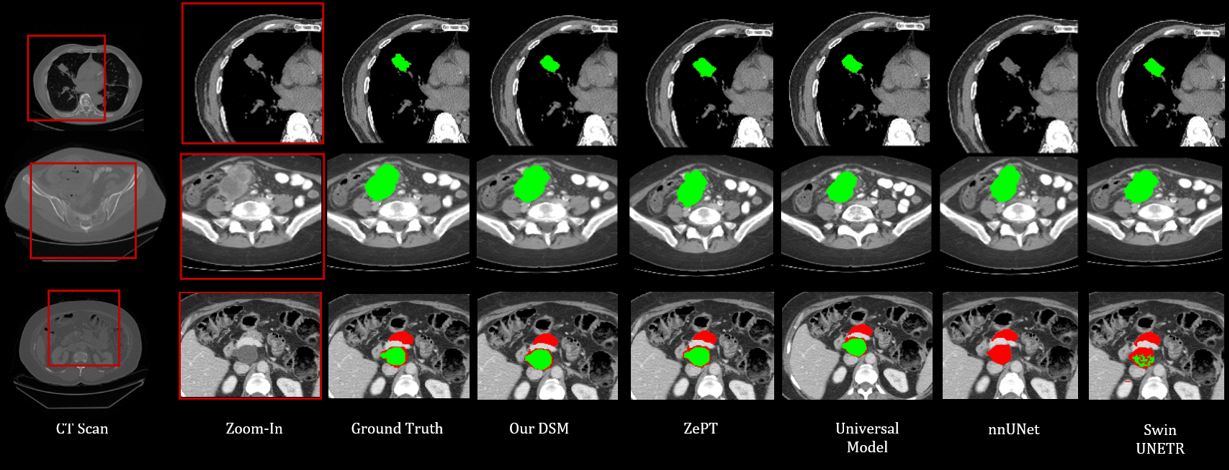

2. dsm.png

Unleashing Diffusion and State Space Models for Medical Image Segmentation

Rong Wu, Ziqi Chen, Liming Zhong, Heng Li, and Hai Shu

Journal of Imaging Informatics in Medicine